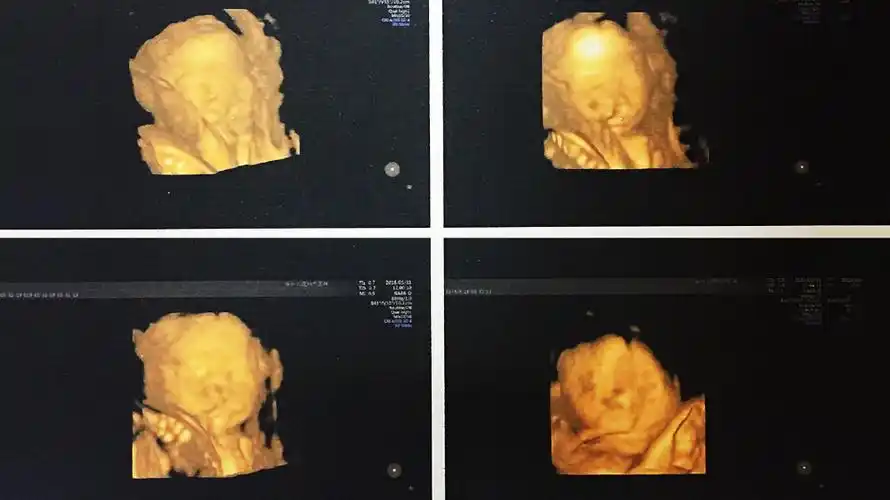

超声诊断胎儿唇腭裂

双胎宝妈21周做四维彩超,筛查出一名胎儿为"唇腭裂"